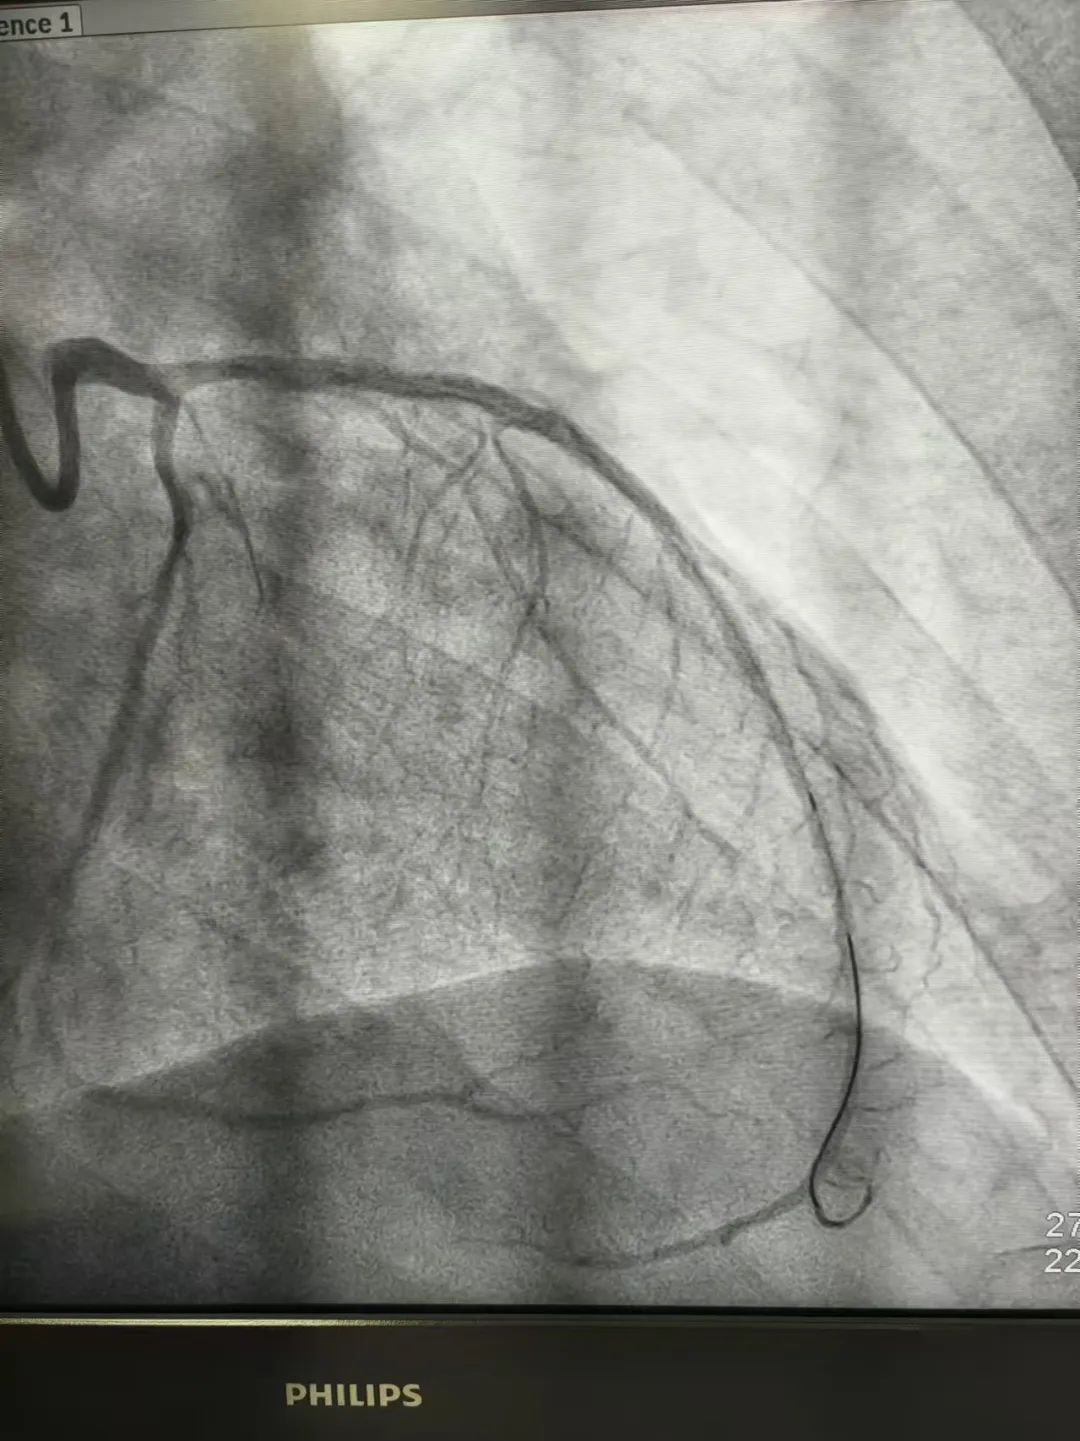

面对这一复杂病情,周玉珍主任团队经过集体讨论,一致认为由于钙化显著,普通扩张效果无法达到治疗效果,决定采用先进的冲击波球囊扩张技术,提高血管的顺应性,为后续支架植入创造更好的条件。在冲击波球囊三次成功扩张后,复查造影显示钙化处管腔得到了良好扩张,随后顺利植入了两枚支架。术后,患者未再出现心绞痛症状,手术取得了圆满成功。

术后造影图像